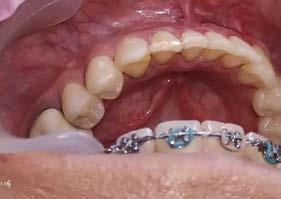

Tienes algunos ejemplares aquí.

Sí, aún no los he revisado, pero tenemos modelos de ortodoncia de la clínica aquí en la universidad. Son interesantes, muestran claramente la forma de pala en algunos incisivos laterales. Tienen una forma muy interesante que es más común en México que en otros lugares. También notamos varias características en los premolares. Hay una gran cantidad de pequeñas diferencias que son cruciales para estimar la población de origen de un individuo.